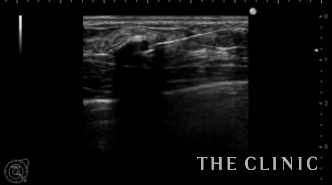

この方は被膜の厚いオイルシストがいくつかありましたが、エコーガイド下に注射針で穿刺吸引しました。

穿刺しました。完全には虚脱しませんが、かなり小さくなりました。